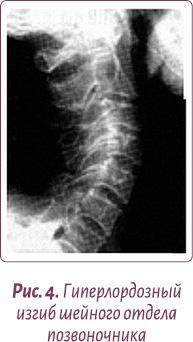

Нормальной статикой шеи считается небольшой физиологический лордоз (прогиб шеи вглубь) (рис. 3).

Чаще всего этот физиологический изгиб гипертрофируется, и шейные позвонки «проваливаются» вглубь шеи — формируется гиперлордоз шейного отдела позвоночника, зажимая нервные окончания и перекрывая кровоснабжение мозга (рис. 4, 5).